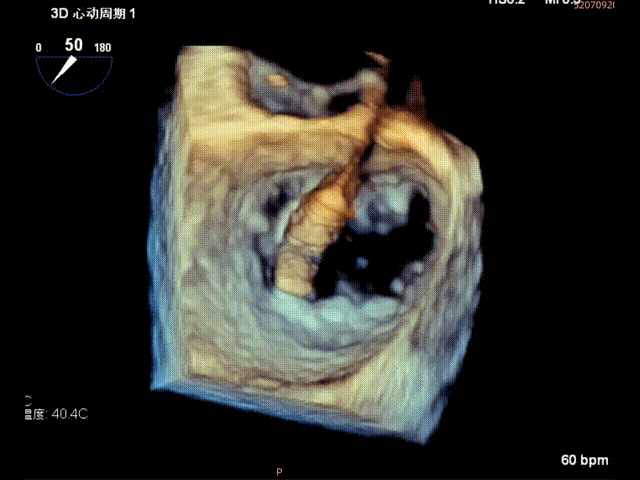

术前食道超声示: 二尖瓣2区前叶大范围脱垂伴后叶栓系。

术前食道超声-2D血流

术前食道超声-3D血流